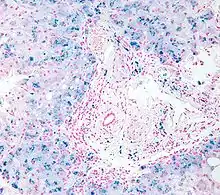

| Micrograph of liver biopsy showing iron deposits due to haemosiderosis. Iron stain. | |

Biopsy

Liver biopsy is the removal of small sample in order to be studied and can determine the cause of inflammation or cirrhosis. In someone with negative HFE gene testing, elevated iron status for no other obvious reason, and family history of liver disease, additional evaluation of liver iron concentration is indicated. In this case, diagnosis of hemochromatosis is based on biochemical analysis and histologic examination of a liver biopsy. Assessment of the hepatic iron index (HII) is considered the "gold standard" for diagnosis of hemochromatosis.